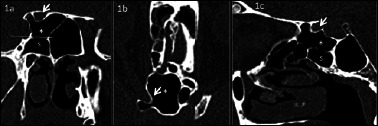

Abstract Image

Methods: In this study, 430 computed tomography scans of paranasal sinuses were analysed to establish the prevalence and different types of Onodi cells. Furthermore, the relationship between Onodi cell and different patterns of sphenoid sinus pneumatisation and surrounding structures were investigated. Special attention was paid to the relationship between Onodi cell and the optic nerve canal, particularly in cases when the optic nerve canal was bulging by more than 50% into the Onodi cell (Type IV).

Results: The Onodi cell was detected in 21.6% of cases, with the most common being Type I (48.5% right, 54.3% left). Type IV bulging of the optic nerve canal into the Onodi cell was observed in 47.1% of cases on the right side, 41.2% on the left side and bilateral in 11.7% of cases.